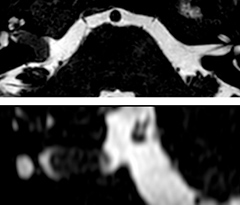

Looking for inflammatory lesions of the spinal cord is usually challenging with MRI, says Dr. Savatovsky. “We solved some of the challenges by implementing sequences such as 3D PSIR, which allows us to see far more lesions than the usual T2 imaging. We are starting to see cases where the MRI images at 1.5T were normal, but then we do see lesions when performing the PSIR at 3.0T.” [1] “Elition also performs very well in imaging of the bony spine, the discs and degenerative disease, especially now that we can include at least one 3D sequence in every scan. For example, we perform a lot of 3D spin-echo (TSE) sequences when imaging degenerative lumbar spines. Thanks to Compressed SENSE and the 3D SpineVIEW protocols, we have a very high signal intensity with no flow voids, so the image quality is very good. The possibility to reformat the images in every plane raises the diagnostic confidence, especially in patients who have to undergo surgery.”